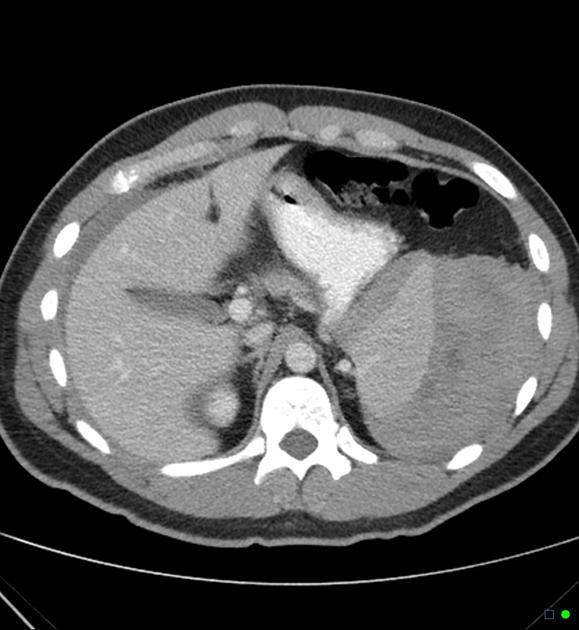

• Chấn thương lách (Splenic trauma)

• Lách lạc chỗ (Splenosis)

• Phân độ chấn thương lách (AAST spleen injury scale)

• Vỡ lách tự phát (Spontaneous splenic rupture)